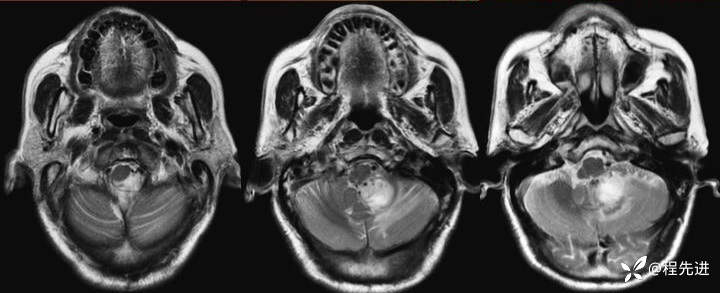

【患者信息】:男,66岁

【现病史及既往史】:头痛半年,行走不稳3个月

T2:

img